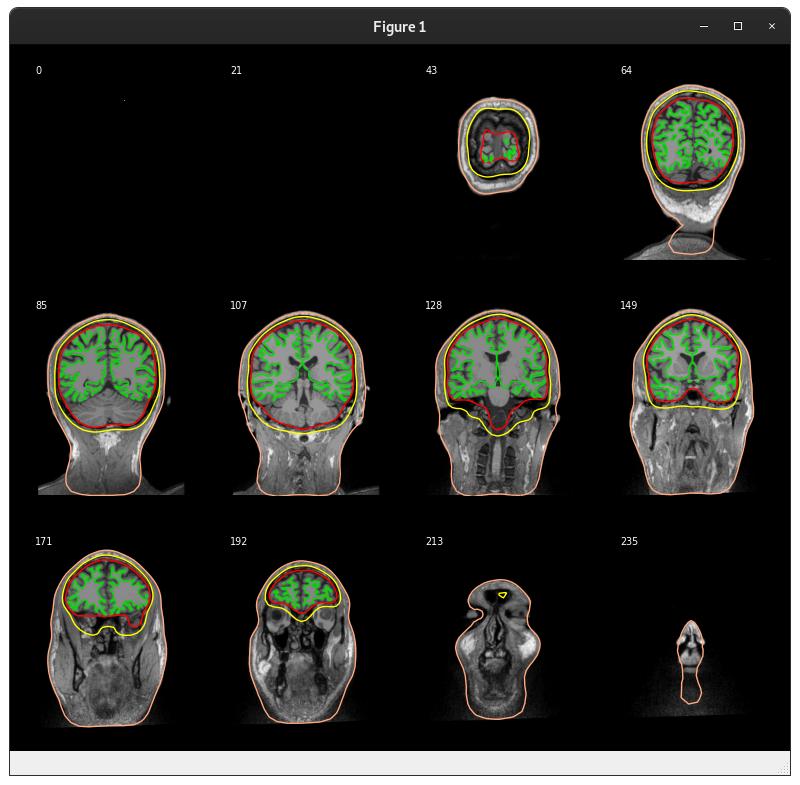

show_orientations=False)mne.viz._3d._plot_mri_contoursthat we should really refactor with themne.viz.misc._plot_mri_contours-- the function names match and there is a lot of similar code so it's unfortunate that we ended up with two copies, presumably due to @agramfort 6 years ago accidentally making two copies in 5c1d64b :)slices=Nonefrom:masterwe correctly avoid the last but not the first and unevenly sample in between, we now evenly sample from near-to-first to near-to-last instead by making 14 points evenly spaced between first and last slice (inclusive) and then excluding the first and last of those 14 to obtain 12.On master for

plot_forward.pywe get:And on this PR:

Note that there is a left-to-right flip here. On

masterthe subject's left was shown on the right (radiological convention, probably not intentional) and this PR sets it to the more standard (for us at least) neurological convention of having the subject's left on the left. You can tell this by the fact that in the image from this PR, slice 177 (bottom left) has the pill on the right, and then the last slice is flipped left-right relative to themasterplots.